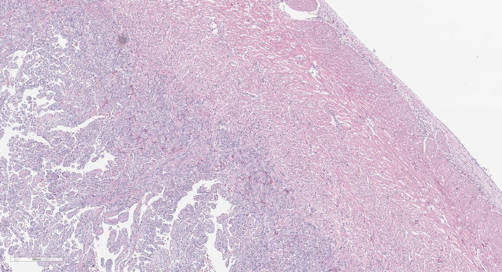

Bildet: Histologibilde som viser betennelsesforandringer i hjertet hos fisk med hjertesprekk